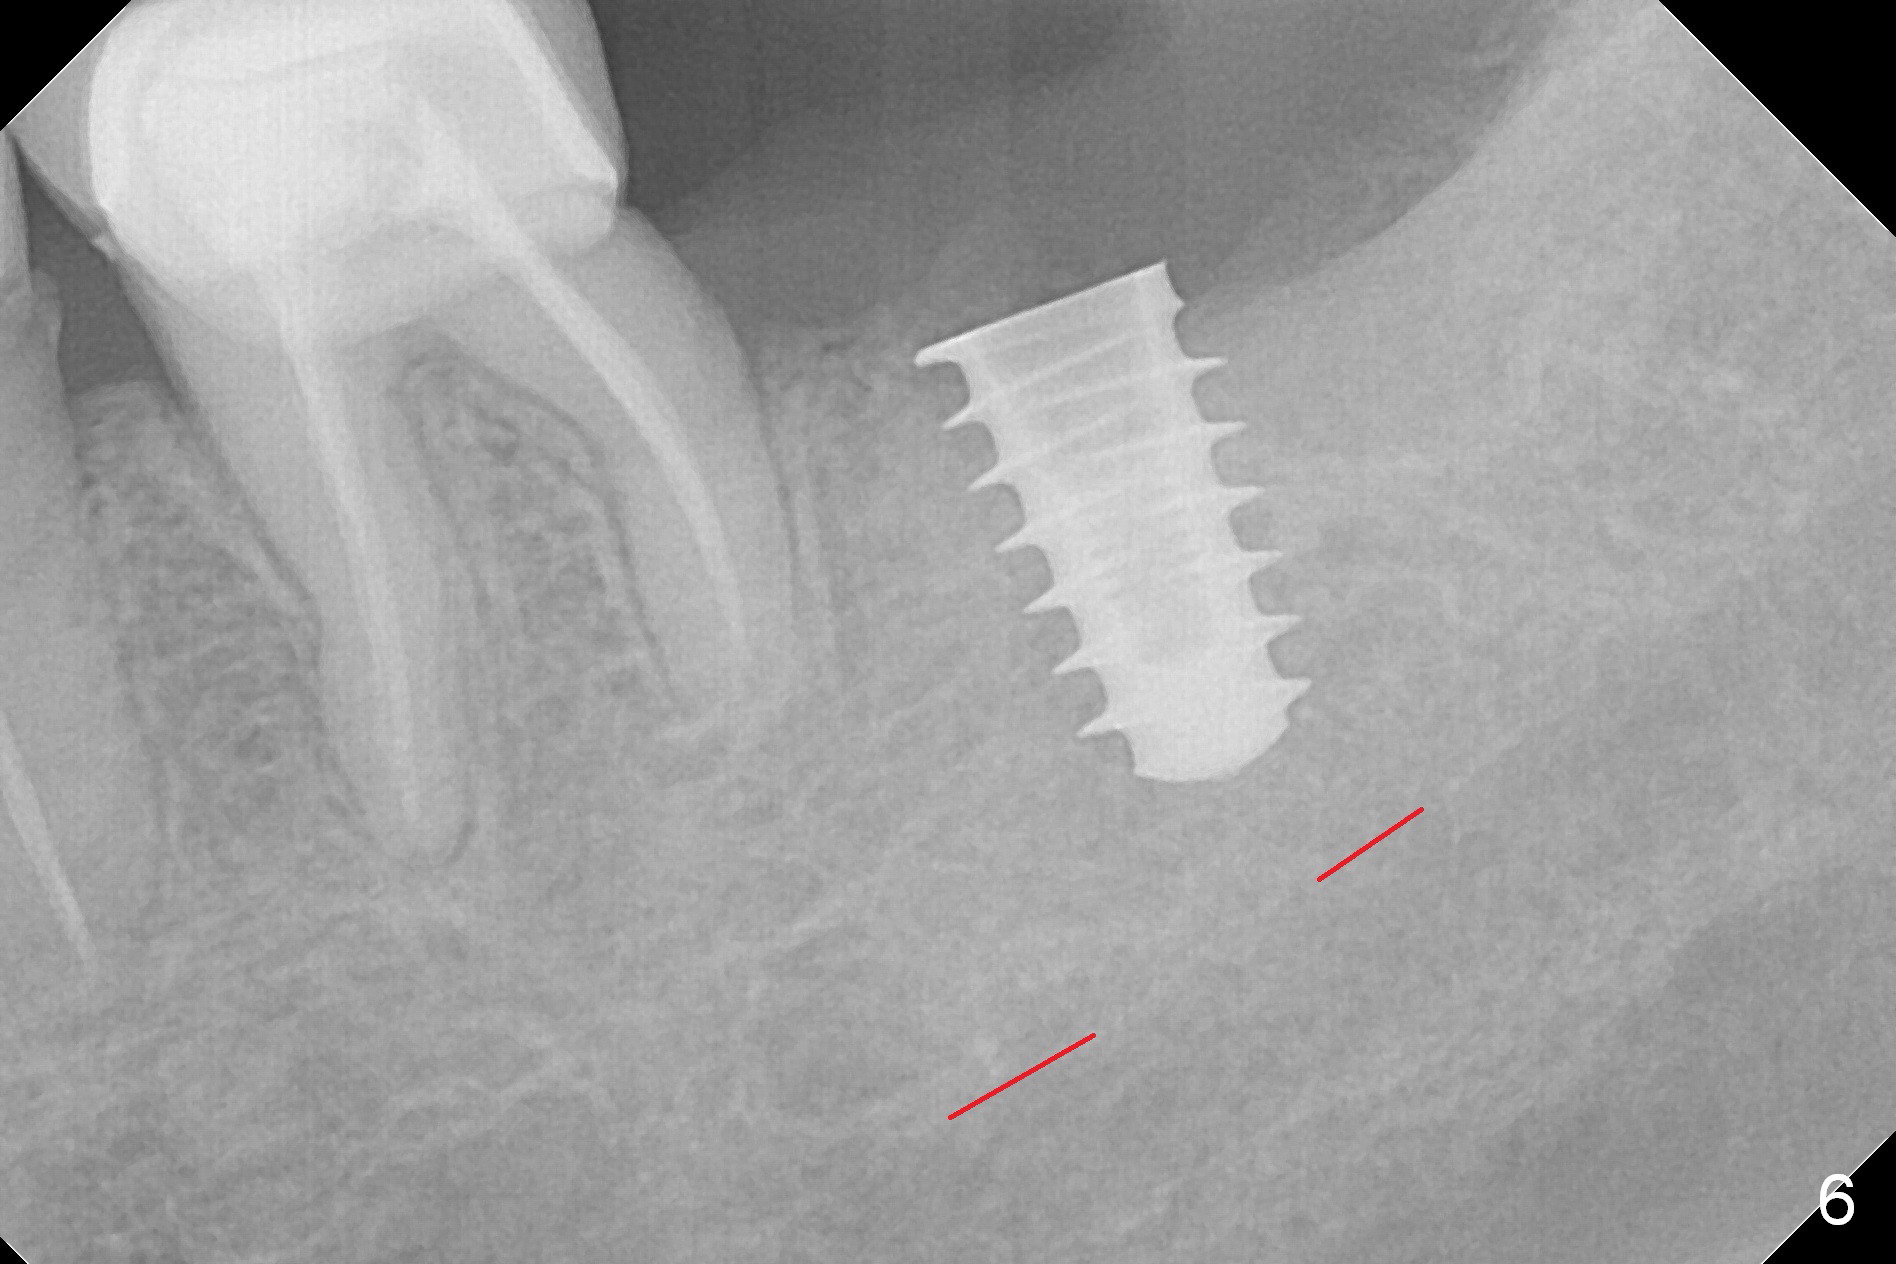

After 1.6 mm pilot drill (Fig.2) and 4.3 mm Magic Drill for 11 mm (gingival margin), a 4.5x11 mm dummy implant is placed with stability (Fig.3). Following Final Drill for 12/13 mm and 4.3 mm MD mesially, a 5x9 mm IBS implant is placed with 40 Ncm (Fig.4). Panoramic X-ray shows the placement is slightly supracrestal (Fig.5). In fact the implant is also placed slightly lingually. When the trajectory is changed, the implant loses stability. When a 5.5x9 mm implant is placed, no stability is achieved (Fig.6). After increase in osteotomy depth for 1-2 mm with MD 4.3 mm, the 5.5x9 mm implant barely obtains stability (~ 10 Ncm, Fig.7). Healing screw is placed. Osteogen plug is inserted in the distal portion of the socket; autogenous bone around the implant and Collagen plug to close the socket opening. Last suture and periodontal dressing are applied.